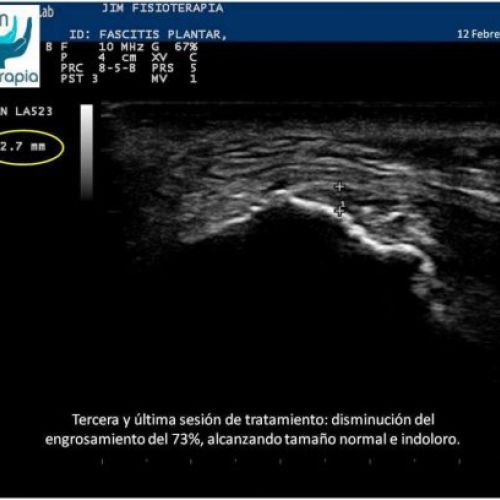

Tratamiento de fascitis plantar con EPI®

Terapia de electrólisis percutánea intratisular EPI® para el tratamiento de la fascitis plantar.